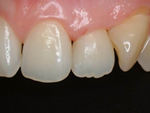

術前

術後